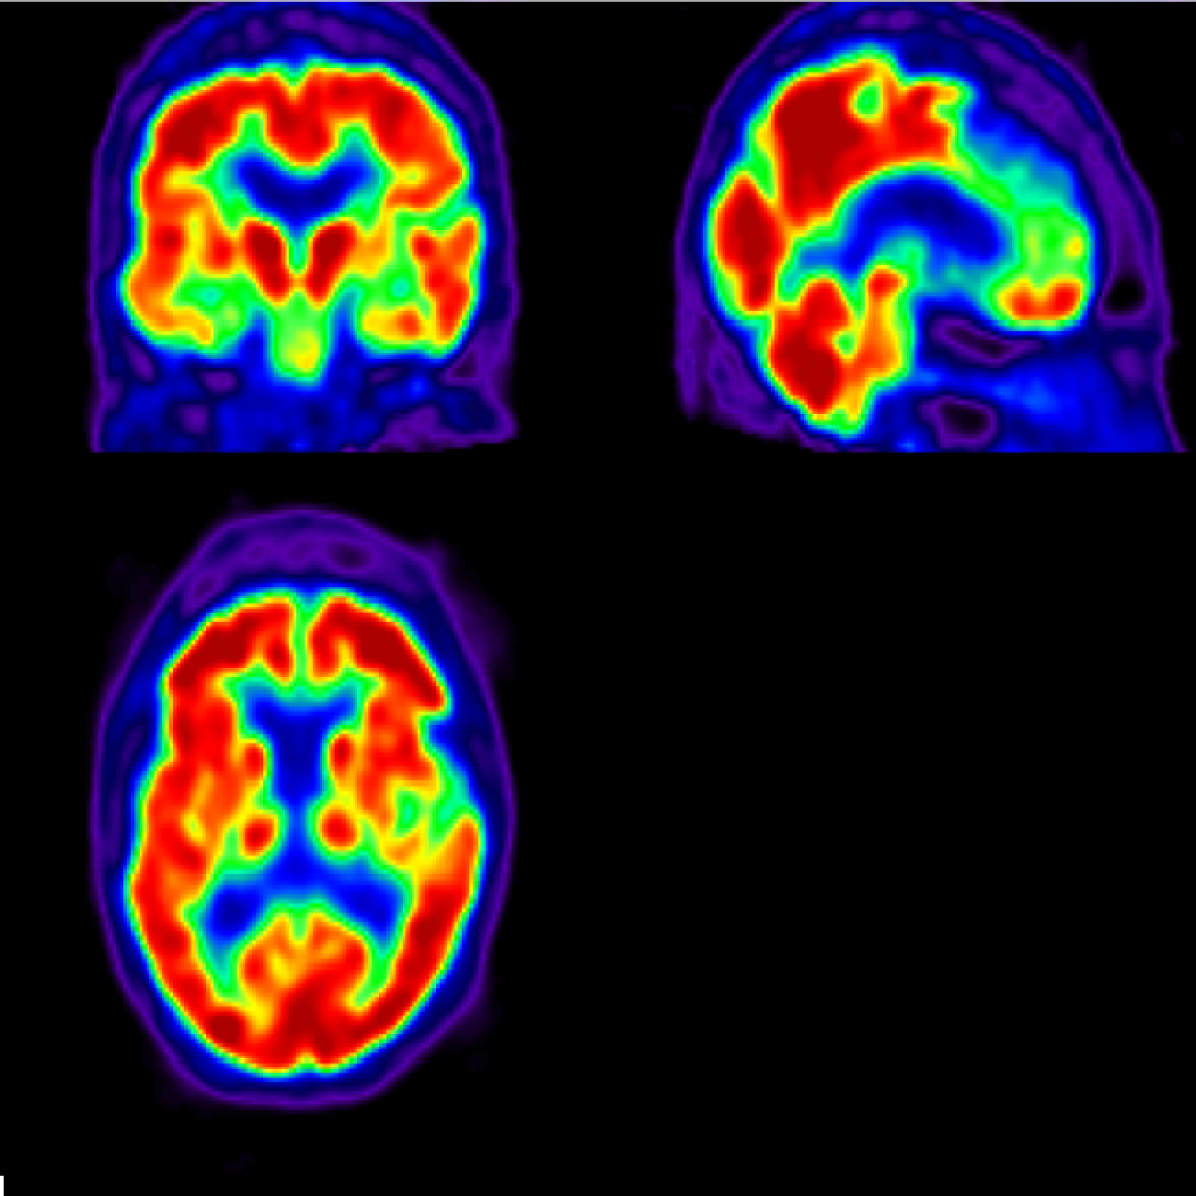

AD main effect is progressive neurological damage resulting from neuronal loss which occurs first in the hippocampus, temporal cortices, and parietal cortices [18, 19] (see Figure 1). As the disease evolves, neural damage progresses and affects the parahippocampal gyrus and amygdala [20]. In advanced stages, AD affects brain regions involved in primary bodily functions, complicating vital movements and becoming fatal to the patient [2]. Caused by the presence of neuritic plaques [21] and neurofibrillary tangles [22] in the affected neurons, this progressive neurological damage translates into neuropsychological and behavioural manifestations including worsened capacity to recall information, problems with planning and decision-making, generalized confusion, delusions, hallucinations, repetition of conversations, anxiety, among others [23, 2]. In addition, AD is typically accompanied by comorbidities such as major depressive disorders [24] which complicate the already poor situation of the patient, aggravating perceived health in a self-sustained downward spiral as proposed by recent life-course models [25] and contributing to severe reductions in life expectancy and other diffuse effects on health and well-being [26].

Refer to caption

(a)

(b)

(c)

Figure 1: Regions of interest for research on early AD diagnosis in the human brain: hippocampus (red), temporal cortices (blue), and parietal cortices (green).